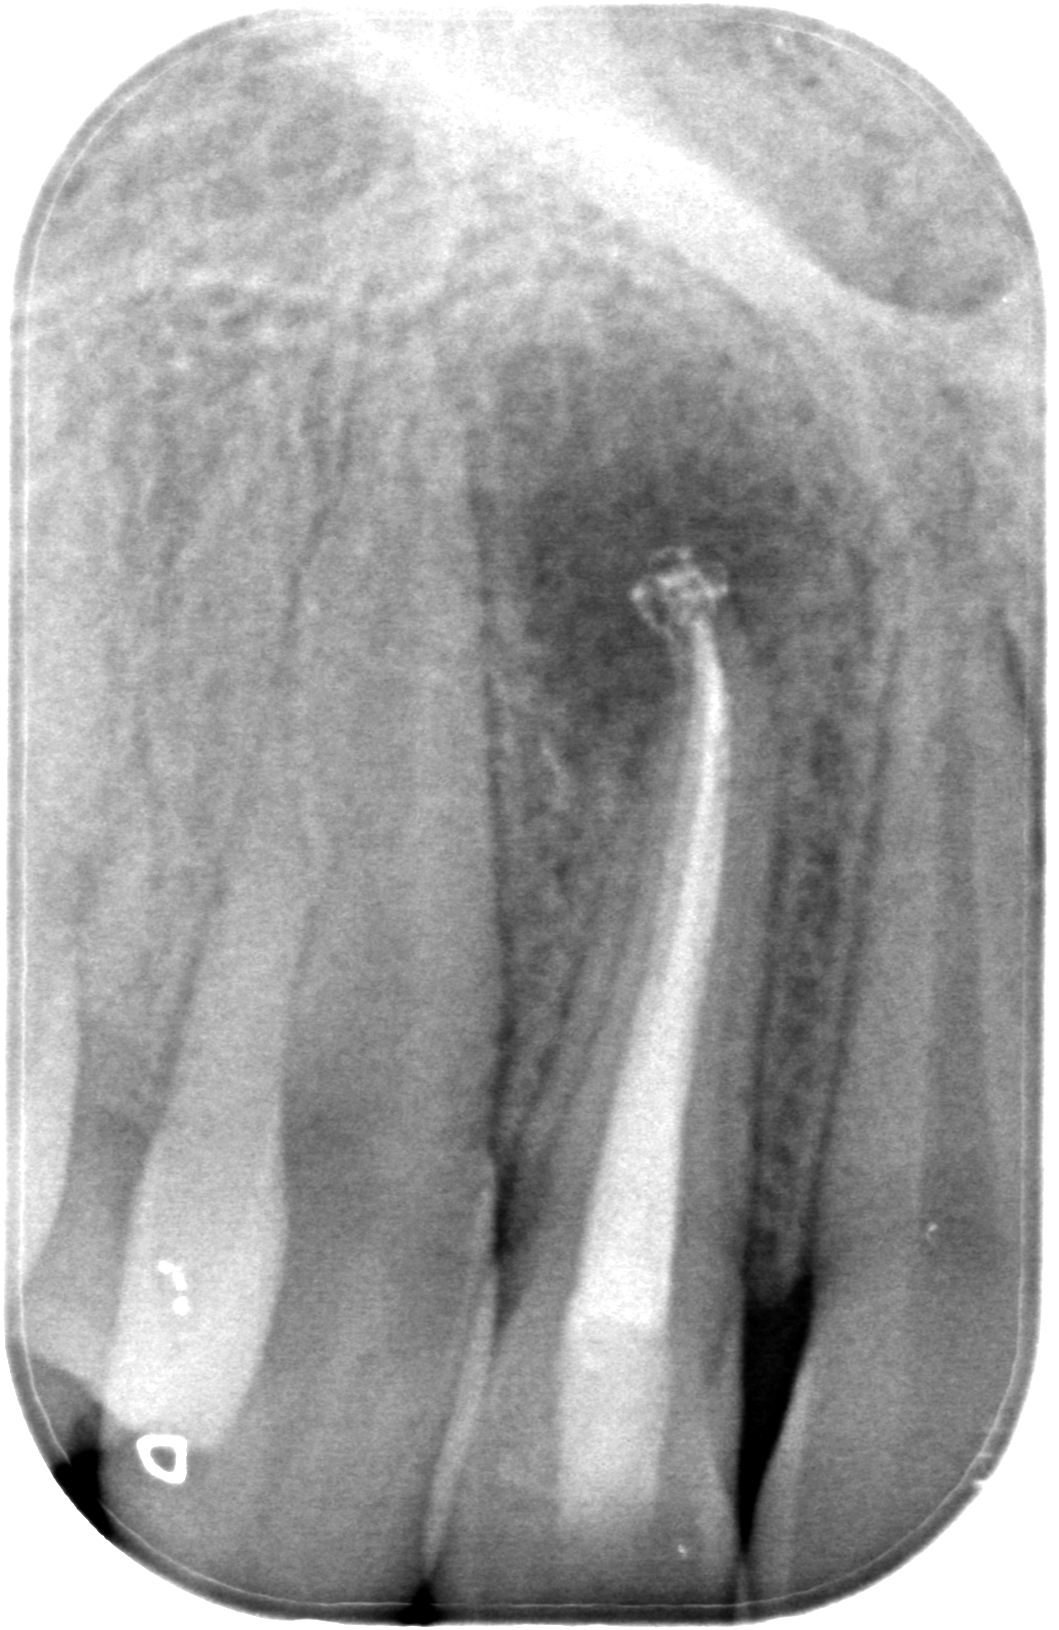

21.04.2023 Patient TG, geb. am 30.03.1974, Zahn 27, WF- Kontrolle 19 Monate post WF